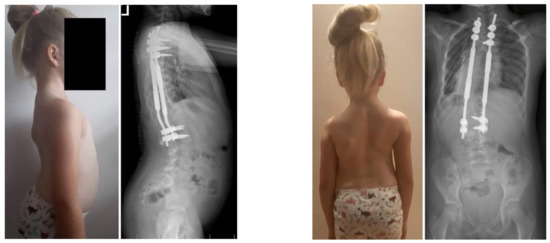

Figure 3.

X-rays and clinical preoperative images.